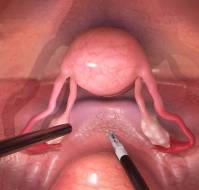

Ovarian torsion is a gynecological emergency caused by rotation of the ovary on its supporting ligaments, leading to compromised blood flow and potential ovarian nec..

Clinical PresentationAn eleven-year-old premenarcheal girl presented with acute lower left abdominal pain and vomiting. On examination, her vital signs were stable, ..